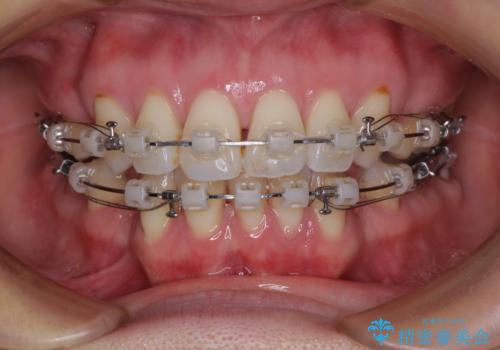

- クリアブラケット

当初目論見通り、左右奥歯の咬み合わせはしっかりとさせることができました。

下唇に跡がつくほど飛び出していた上顎前歯も引っ込み、満足のいく仕上がりとなりました。